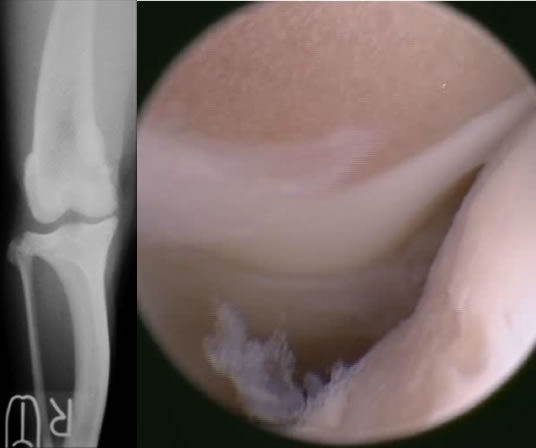

前十字靭帯断裂とは

膝関節の安定化を担っている前十字靱帯が断裂することにより、膝関節の不安定性が発現します。断裂した前十字靱帯の断端から炎症性のメディエーターが放出されるため、関節炎が起こります。

診断

触診、レントゲン検査、関節鏡検査

治療

関節外制動法(Lateral Suture Stabilization)など。前十字靭帯と同様の働きをする位置に合成靭帯を設置し、膝関節を安定化させる手術法。